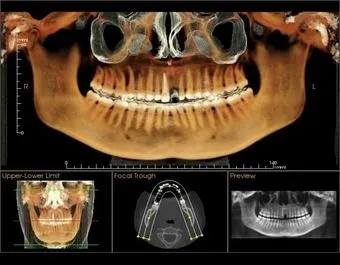

3D Imaging Technology provides three-dimensional imaging to the dental community, right in the practice office. The system offers active sagittal, coronal, and axial viewing and manipulation. It enhances diagnosis and treatment planning by providing more accurate imaging. Using the 3-D mapping tool, dental professionals can easily format and select desired slices for immediate viewing. Cone Beam imaging delivers quicker and easier image acquisition a typical scan takes only 20 seconds.

• Allows doctors to visualize anatomy that can not be diagnosed externally or in 2 dimensional images.

• Thorough diagnostic information (optimum view of the critical anatomy of all oral and maxillofacial structures.)